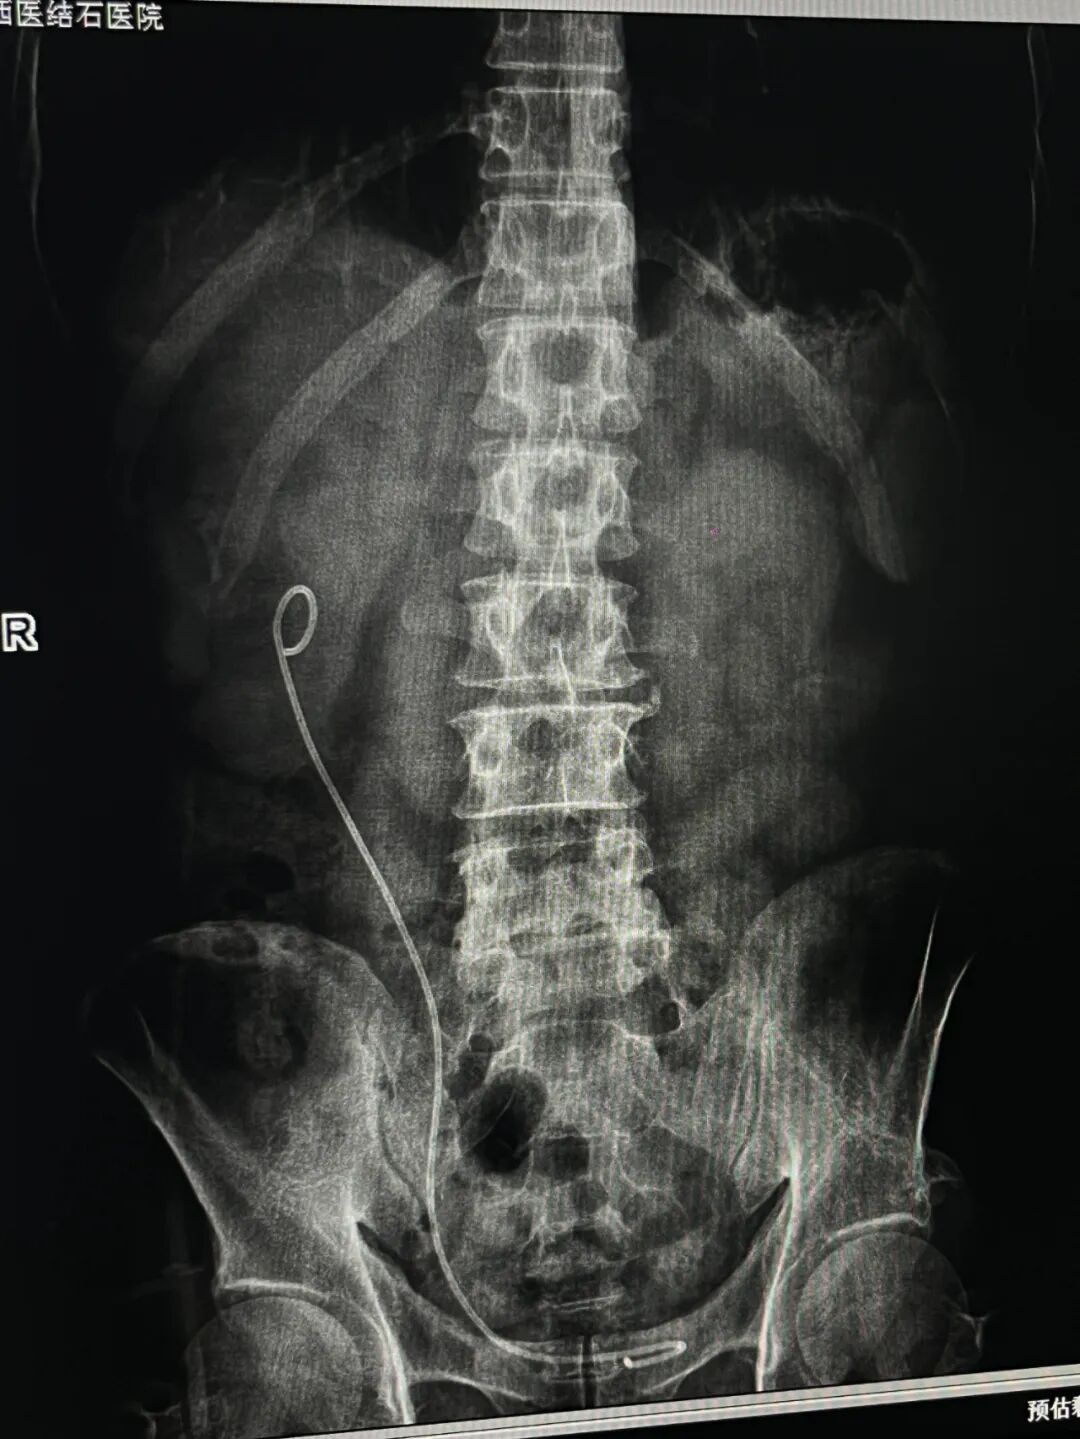

在左侧症状得到有效控制后,医疗团队着手准备第二阶段的治疗。针对右侧较大的肾结石,团队制定了经皮肾镜碎石取石的手术方案,并完成了包括麻醉评估、手术路径规划、并发症预案及术后康复计划在内的详细术前准备。此后,患者在全身麻醉下接受了经皮肾镜下右肾结石钬激光碎石取石术,同期完成了输尿管支架管置入等操作。手术按计划进行,术后患者生命体征平稳,安返病房。